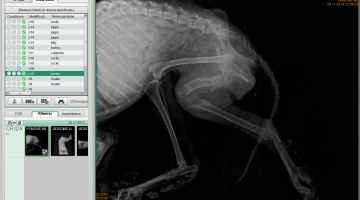

In alcuni casi la radiologia si avvale dell’impiego di mezzi di contrasto per visualizzare immagini altrimenti “radiotrasparenti”, per evidenziare meglio alcune lesioni, il percorso di vasi o delle vie urinarie. In diverse occasioni in campo veterinario l’esame radiografico viene eseguito su pazienti in stato di sedazione. Questo perché per ottenere immagini di qualità elevata è necessaria l’immobilità assoluta dell’animale il cui corpo deve essere posizionato secondo protocolli ben precisi e di difficile realizzazione in stato di veglia. A tale scopo la sala radiologica del nostro ambulatorio è dotata anche di impianto di anestesia gassosa.

Attualmente la nostra struttura è munita di un apparecchio radiologico digitale indiretto Fuji. (Nella photogallery in basso). I vantaggi di questa tecnologia rispetto alla radiologia “analogica “ tradizionale sono molteplici. Primo fra tutti la qualità dell’immagine e la possibilità di ingrandire i particolari, correggere i contrasti, visualizzarla in negativo, ma anche misurare con precisione i dettagli. Poi la notevole riduzione dei tempi dello studio radiografico che in campo veterinario significa anche la riduzione dei tempi di anestesia del paziente con beneficio per la sua salute. Le lastre digitali non inquinano l’ambiente. Sono dei files che possono essere trasmessi per posta elettronica, masterizzati su cd o pennette di memoria da mettere nella cartella clinica da consegnare al proprietario del paziente e, nel caso della nostra struttura allegati in rete e nella scheda clinica dell’animale.